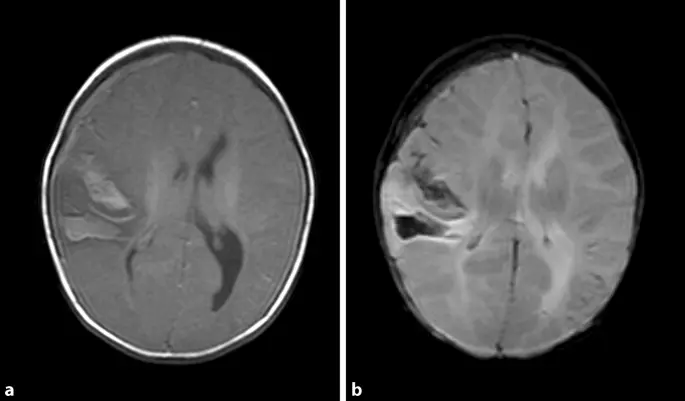

- Blutungen: Blutungen im Gehirn, zum Beispiel durch eine Hirnblutung, können zu einem Hirnödem führen.

- Gehirnschäden: Ein Hirnödem kann zu dauerhaften Gehirnschäden führen, die zu Entwicklungsstörungen, Lernschwierigkeiten und Behinderungen führen können.